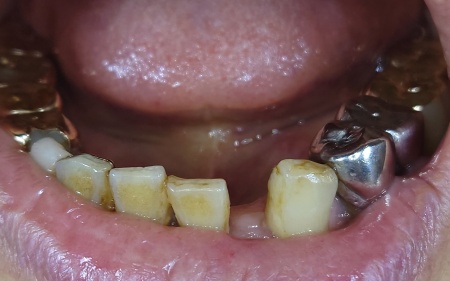

拝見したところ、左上の4番目の歯(第1小臼歯)の根が割れて、痛みと歯ぐきの炎症が認められました。

まず、左上の歯を抜歯します。

続いてインプラント埋入手術を実施し、インプラントを正しい位置と角度であごの骨に埋入しました。